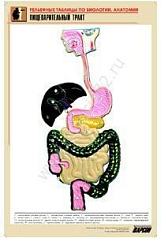

8. Пищеварительный тракт;